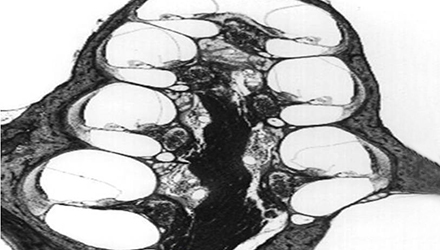

梅尼埃病是以膜迷路積水為基本病理改變,以發(fā)作性眩暈、聽力下降、耳鳴和耳脹滿感為臨床特征的特發(fā)性內(nèi)耳疾病。

單側(cè)發(fā)病患者約占85%,累及雙側(cè)者常在3年內(nèi)先后發(fā)病,發(fā)病年齡大多在30~50歲,無明顯性別特征。

膜迷路積水致膜迷路脹破,內(nèi)外淋巴液混合,刺激神經(jīng)感覺細胞導致眩暈、耳鳴、耳聾,裂口愈合則病變暫時恢復。下圖左為前庭膜膨大,右圖為前庭膜破裂,內(nèi)外淋巴交混。